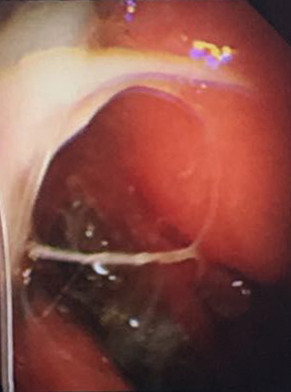

大量藍(lán)斑、黏連帶

我院呼吸內(nèi)科采用改良型“軟式胸腔鏡”,該新設(shè)備軟硬結(jié)合,前端可彎曲,能多方向觀察胸腔內(nèi)改變,比老式“硬式胸腔鏡”的探查視野更大,診斷更準(zhǔn)確。